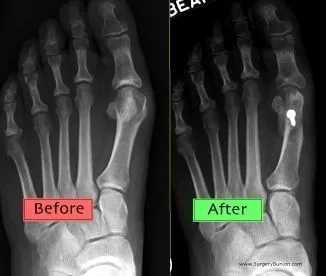

Bunions are readily apparent – the prominence is visible at the base of the big toe or side of the foot. However, to fully evaluate the condition, the foot and ankle surgeon may take x-rays to determine the degree of the deformity and assess the changes that have occurred.

A variety of surgical procedures is available to treat bunions. The procedures are designed to remove the “bump” of bone, correct the changes in the bony structure of the foot, and correct soft tissue changes that may also have occurred. The goal of surgery is the reduction of pain.

In selecting the procedure or combination of procedures for your particular case, the foot and ankle surgeon will take into consideration the extent of your deformity based on the x-ray findings, your age, your activity level, and other factors. The length of the recovery period will vary, depending on the procedure or procedures performed.